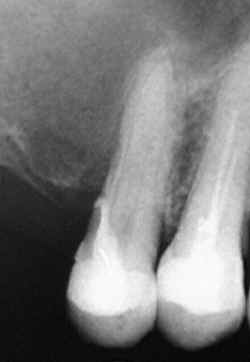

CASO II